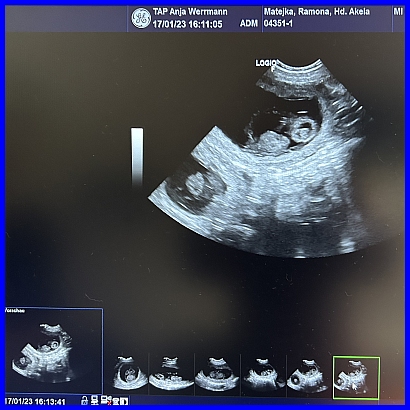

Da ist ein Baby, sieht eigentlich eher wie eine Maus aus, aber eine süße! :-)

Hier sind ganz eindeutig zwei gefüllte Fruchtblasen zu erkennen, in der oberen sieht es sogar fast wie ein Körper aus, aber das täuscht. Es ist der 31. Tag der Trächtigkeit, Halbzeit.